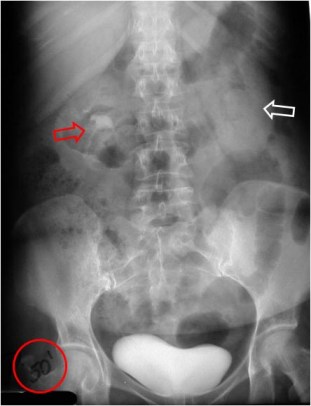

SIGNO DE LA VEJIGA DE PERA

Los traumatismos pélvicos, las adenopatías ilíacas bilaterales, la lipomatosis pélvica y otros procesos, producen una compresión bilateral de la vejiga, que adopta forma de lágrima o de pera.

En la imagen vemos la vejiga de pera en un paciente con traumatismo pélvico. Puede verse la fractura de la rama iliopubiana izquierda y la fractura de ala sacra con luxación sacroilíaca izquierda.